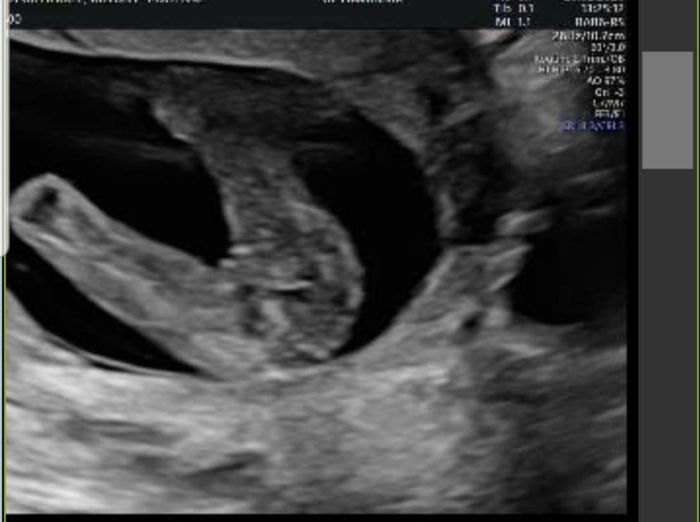

Hola! Quería preguntaros si entendéis el método Ramzi si sabéis que puede ser. Os lo agradecería muchísimo. Es una ecografía de 7 semanas